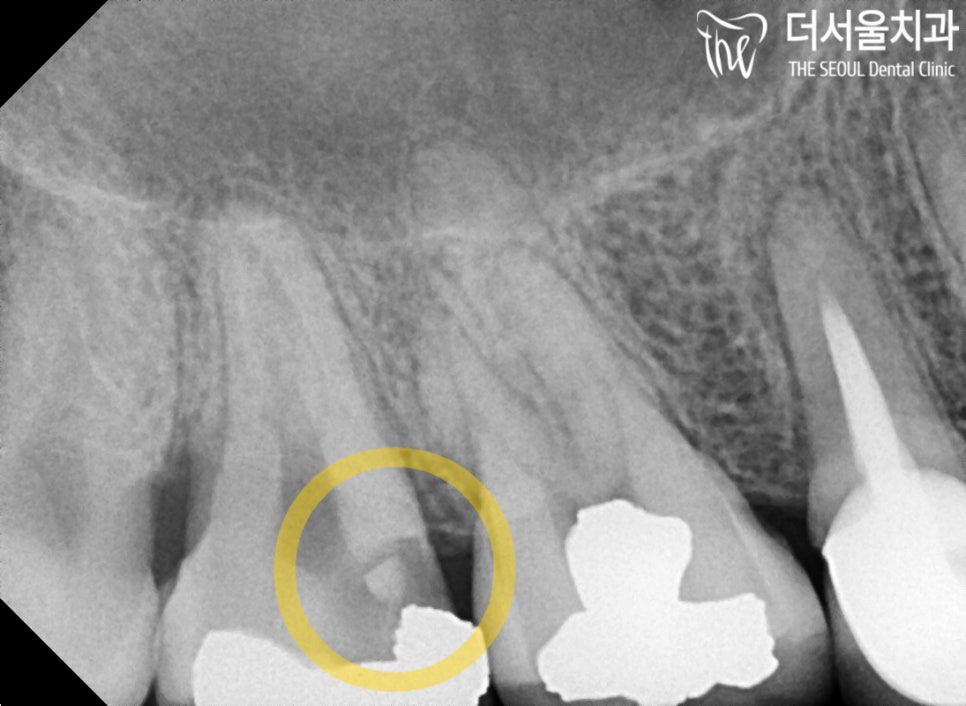

『아말감 하방으로 생긴 충치』

환자께서는 위쪽 어금니에

극심한 통증 을 느낀 채로

더 서울을 내원하셨습니다.

일단 현재 상황을 자세히 파악하기 위해

정밀 진단을 진행하기로 했습니다.

육안 관찰 결과,

통증 이 생긴 곳에 아말감으로 추정되는 것이

씌워져 있는 것을 확인할 수 있었습니다.

음.. 일부분이 깨져있었는데요.

별로 상황이 좋지만은 않았습니다.

좀 더 자세히 살펴보기 위해

파노라마 촬영을 진행한 결과.

단 몇 개월이라도 일찍 내원을 하셨더라면

이런 일까지 벌어지지 않았을 텐데..

참 아쉬움이 드는 건 어쩔 수 없나 봅니다 ㅎㅎ